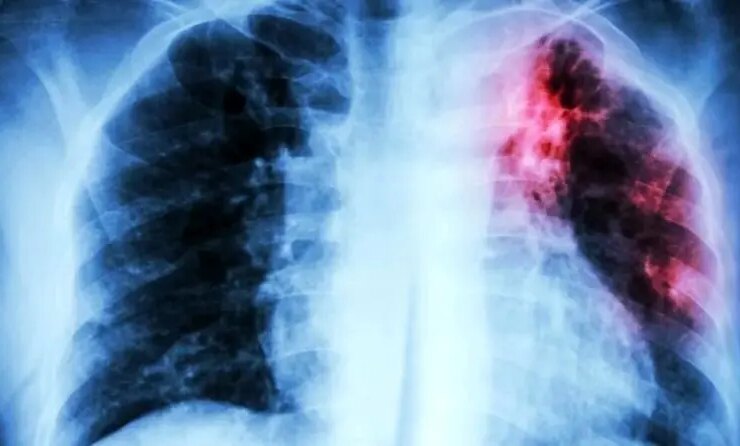

سازمان بهداشت جهانی (WHO) اعلام کرد که سل همچنان به عنوان کشنده ترین بیماری عفونی در جهان جایگاه مرگبار خود ...